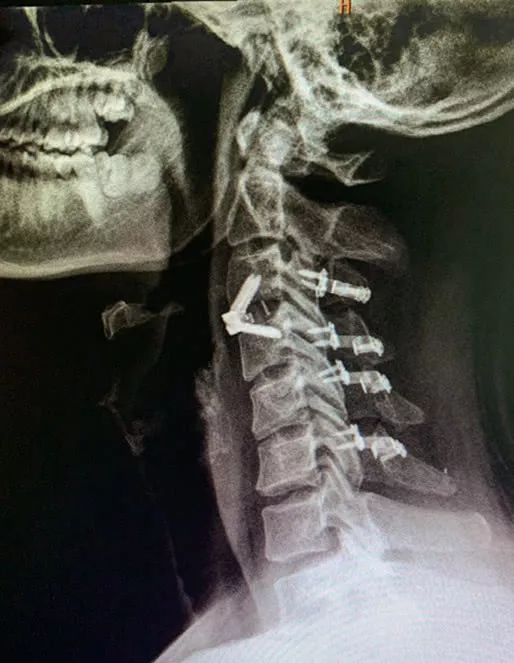

伍先生的頸椎間盤嚴(yán)重突出

左側(cè)神經(jīng)根嚴(yán)重壓迫

隨后,醫(yī)生為其

制定手術(shù)方案

終于,通過(guò)手術(shù)

伍先生的頸椎突出椎間盤壓迫

已被解除

術(shù)后配合藥物、高壓氧、

康復(fù)針灸理療及功能鍛煉

在醫(yī)護(hù)人員精心護(hù)理下

伍先生左側(cè)上下肢體逐漸恢復(fù)活動(dòng)

終于,在術(shù)后半月能下地行走